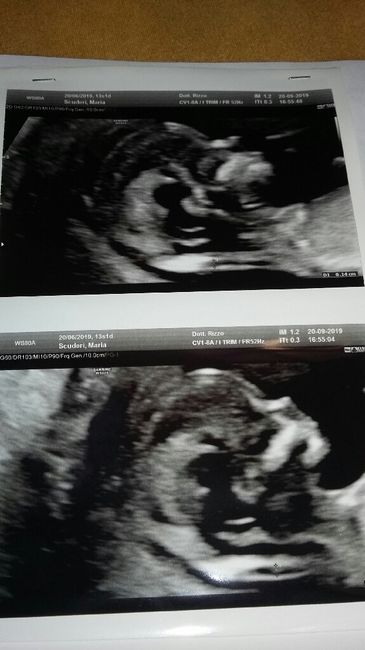

di down......mi consigliano di fare l'esame del DNA fetale che farò lunedì prossimo, però l'ansia mi sta assalendo.....C'è qualcuna che ha avuto la mia stessa esperienza e poi dal risultato del test del dna fetale era tutto ok????Allego foto di referto ed ecografia